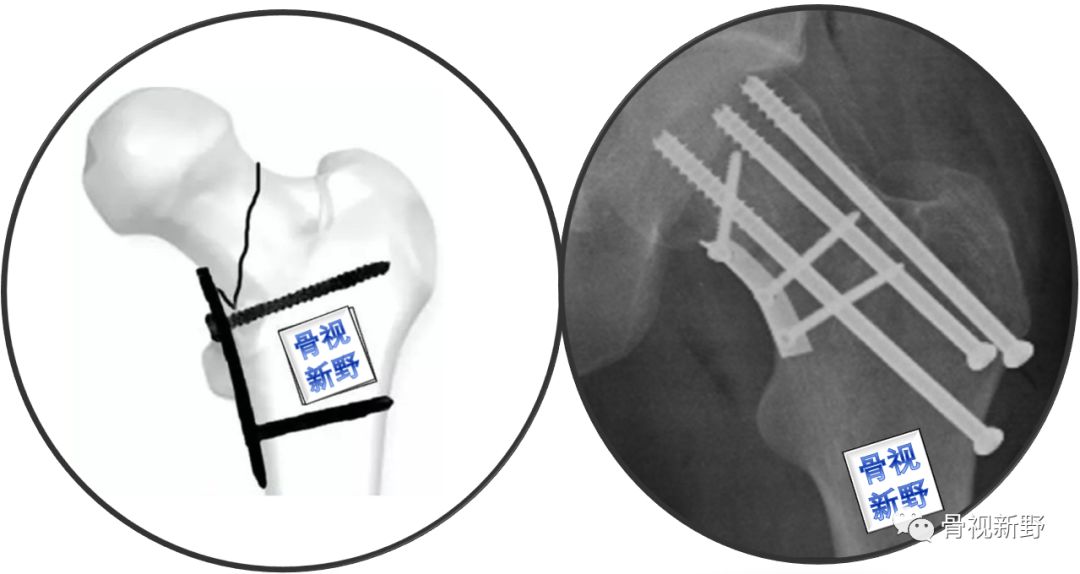

优化固定新理念——第4枚横形拉力螺钉(The 4th tranverse lag scew )

第4枚横形拉力螺钉垂直于Pauwels Ⅲ型骨折线,能对垂直的骨折面起到加压作用,可明显增加平行螺钉固定的稳定性。

在股骨颈内后侧粉碎骨折者,骨折不稳定,增加第4枚横形螺钉也可明显增加固定的稳定性。